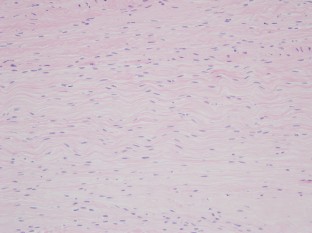

Fig. 1

Retrospective analysis was performed for all patients who underwent Achilles tendon repair for acute Achilles tendon rupture at our institution between 2008 and 2015. The presence of Achilles tendinosis was determined by light microscopic histology of ruptured Achilles tendons. Patients were grouped according to the presence of Achilles tendinosis and patient demographics, sports activities, and clinical outcomes were compared. Ankle activity score was used to evaluate the level of sports activity and Achilles tendon total rupture score (ATRS) was used to evaluate clinical outcomes.

A total of 152 Achilles tendon ruptures were included: 112 (77%) showed Achilles tendinosis at a ruptured Achilles tendon on histology and 40 (23%) did not. Patients who had no Achilles tendinosis prior to rupture had a lower ankle activity score (P < 0.05) and higher incidence of non-sports related injury (P < 0.05). ATRS was not significantly different between the groups at final follow-up (P = n.s.).